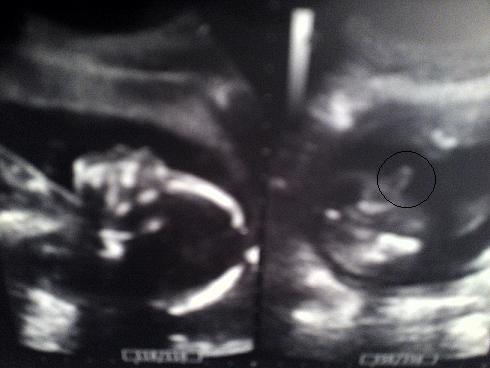

Also wenn du es wissen willst und dein Kind es zeigt, dann kann es der Arzt ganz sicher sagen!! *g* Vorausgesetzt es lässt sich zwischen die Beine schauen!! Hier mal das Beweisfoto von usrem Sohnemann!! *g* War um die 20 SSW rum glaub ich!!

Bild zu